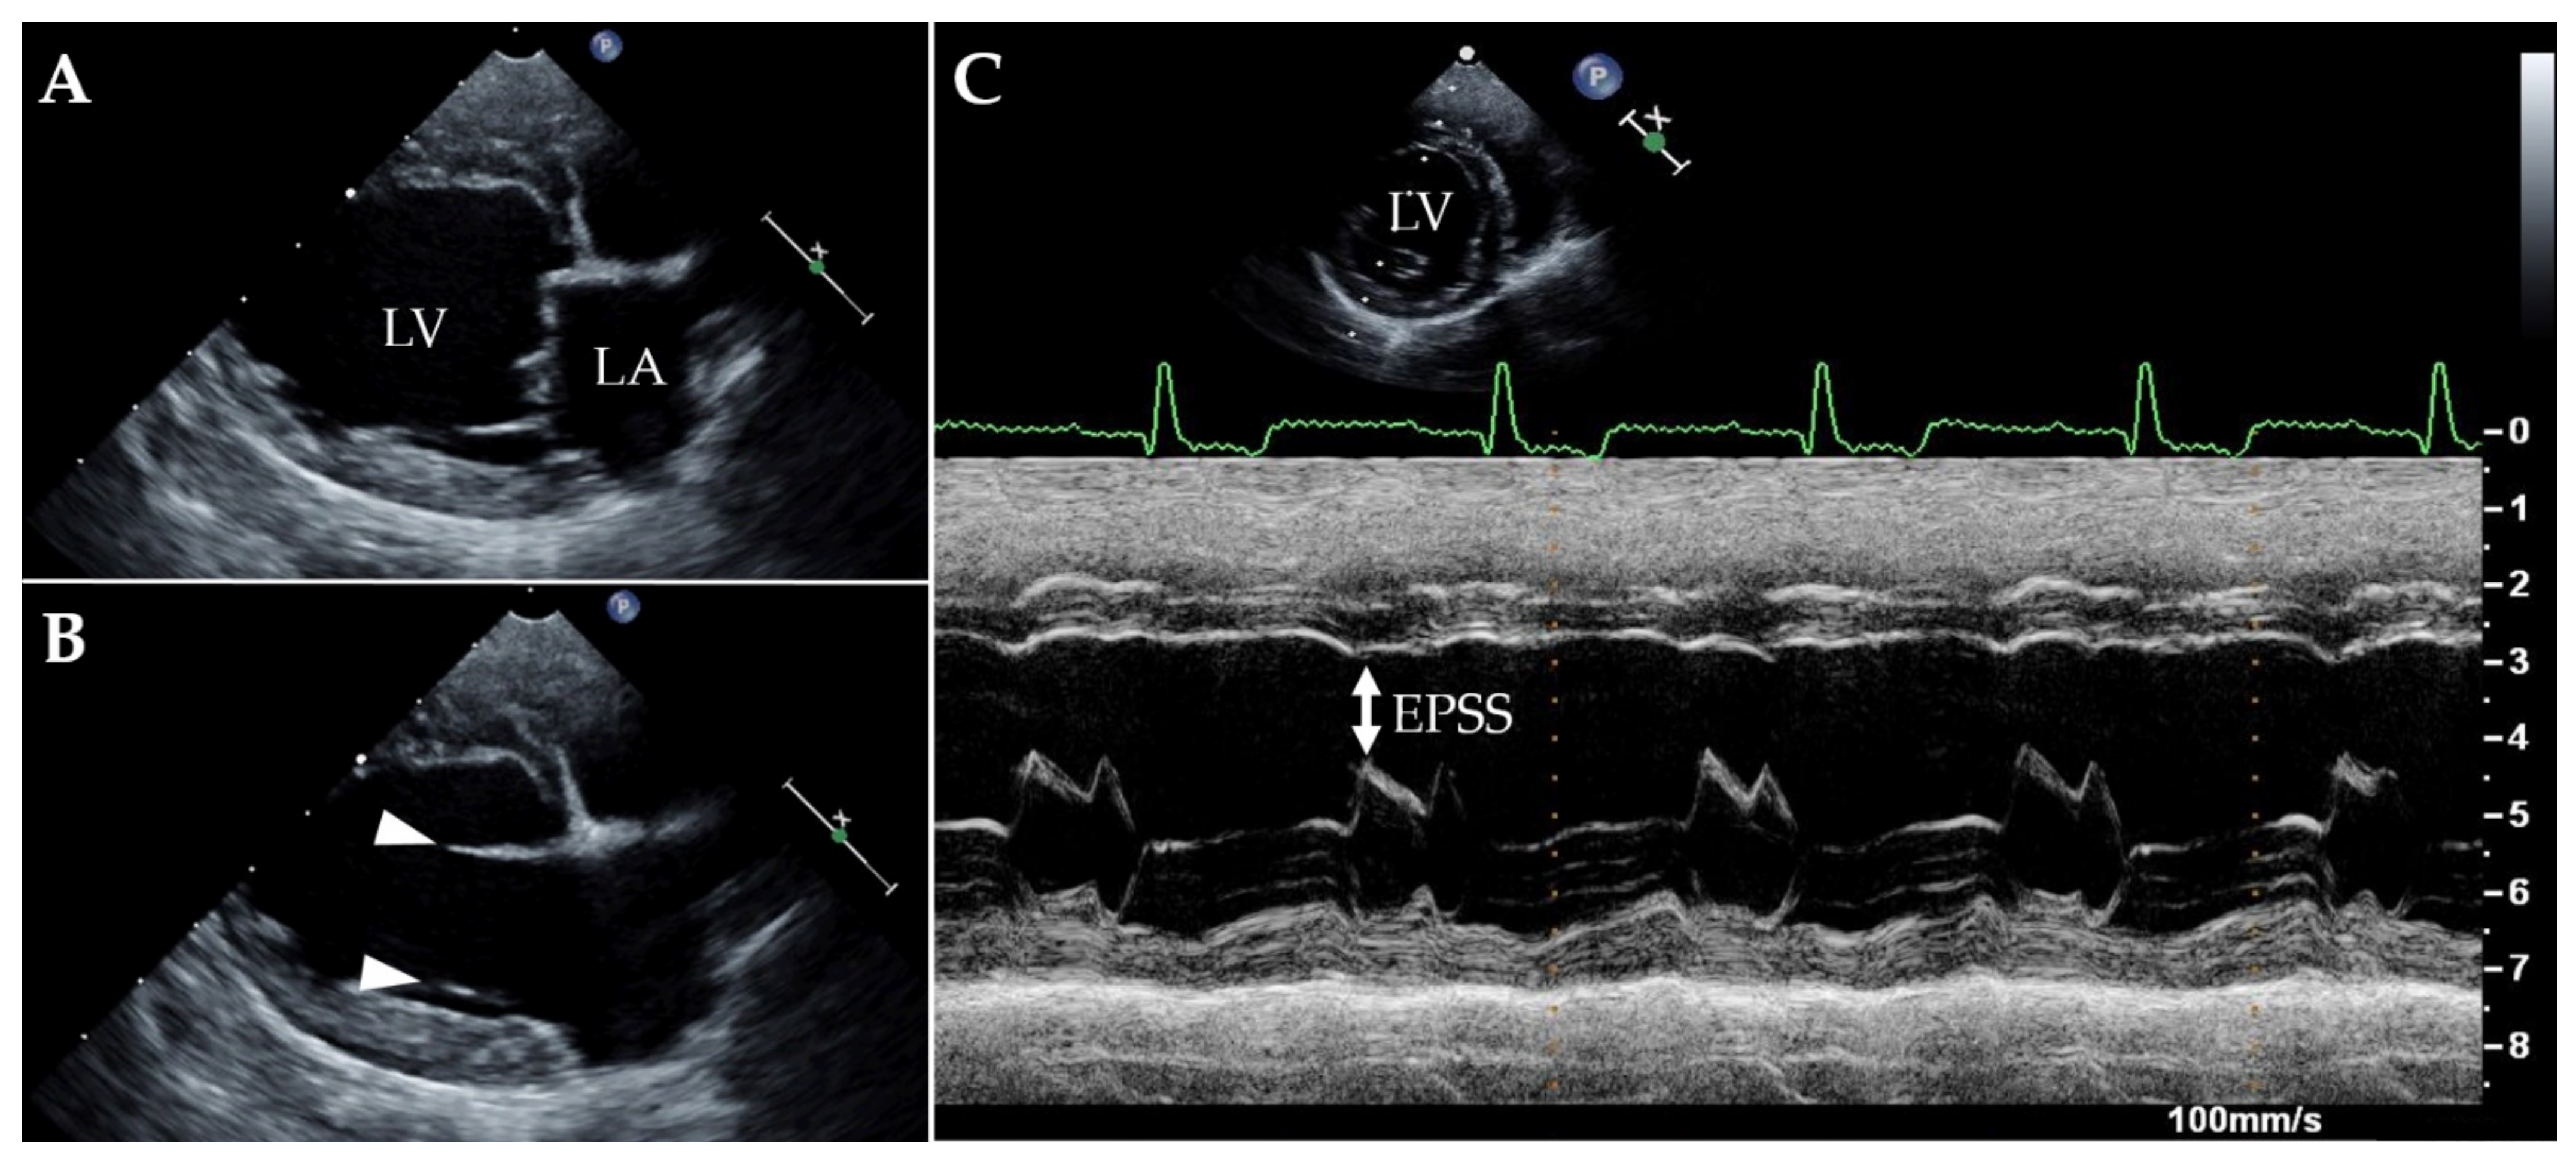

| LA/Ao | 1.2 | 1.15 | <1.6 a |

| LAD (mm) | 30 | 28 | 22.1–33.1 b |

| LVIDDn | 1.95 | 1.9 | 1.27–1.85 c |

| LVIDSn | 1.64 | 1.48 | 0.71–1.26 c |

| EDVI (mL/m2) | 148 | 126 | 49.8–122.4 d |

| ESVI (mL/m2) | 96 | 70 | 13.2–38.0 d |

| SF (%) | 16 | 22 | 30–49 d |

| EF (%) | 35 | 45 | 57.8–82.1 d |

| EPSS (mm) | 12 | 9 | <6.5 e |